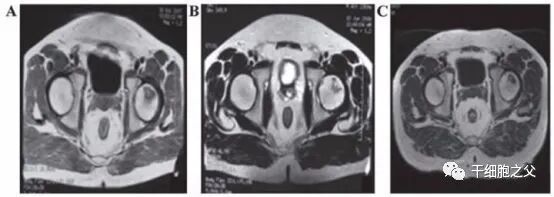

• 应用脐带MSC治疗股骨头坏死

吉林省组织工程重点实验室刘颖教授、首都医科大学宣武医院谷涌泉主任等,对9位骨循环协会评级为II-IIIa级的股骨头坏死患者经大腿动脉输注脐带间充质干细胞后,患者的红细胞、血小板、血氧转运指数明显改善。MRI检测显示24个月后股骨头坏死区域体积显著减少。

图片

推荐阅读:临床进展|干细胞疗法针对65例股骨头坏死的案例报告